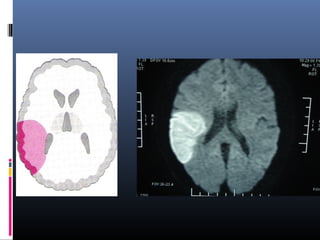

(b–e) Perfusion CT maps of MTT (b), CBF (c), and CBV (d) and a summary

map (e) show altered MTT and CBF in the right frontotemporal area, suggestive of

ischemia, and a small subcortical area with decreased CBV, suggestive of an

infarcted core. Note the area of increased CBF and CBV in the right caudate and

lenticular nucleus, representing the first stage of brain ischemia (compensatory

supply with cerebrovascular reserve). Thus the potential salvageable brain tissue is

equivalent to CBF minus CBV

Thus the potential salvageable brain tissue (green) is equivalent

to CBF minus CBV

Follow-up axial T2-weighted MR image shows a hyperintense right

front parietal area and caudate nucleus related to final infarction in the

ischemic area (both decreased and increased flow areas at perfusion CT),

which resulted because no treatment was performed